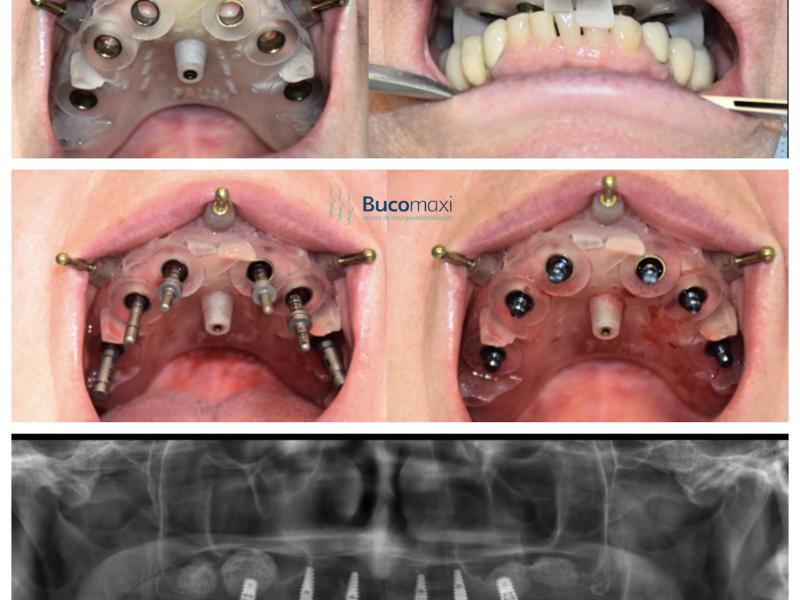

Cirurgia guiada é uma tecnologia avançada que permite aos cirurgiões realizarem procedimentos cirúrgicos com maior precisão e segurança. Esta tecnologia envolve a utilização de um sistema de navegação guiado por computador que fornece informações importantes ao cirurgião durante o procedimento cirúrgico. Os médicos utilizam o sistema de navegação para criar e acompanhar um plano cirúrgico preciso, o que permite que eles executem o procedimento com maior precisão e segurança.

O sistema de navegação de Cirurgia Guiada é composto por vários dispositivos que permitem que o cirurgião monitore a localização de instrumentos cirúrgicos no corpo do paciente durante o procedimento cirúrgico. Estes dispositivos incluem sensores de movimento, imagens de raios-X, ultrassom e até dispositivos laser. A Cirurgia Guiada permite que o cirurgião use um monitor para visualizar e acompanhar a localização de instrumentos cirúrgicos dentro do corpo do paciente.

Além da precisão, a Cirurgia Guiada também proporciona ao cirurgião um melhor entendimento da anatomia do paciente. Isso é possível graças ao uso de imagens de raios-X ou ultrassom durante o procedimento, o que permite que o cirurgião visualize o interior do corpo do paciente. Isso torna possível para o cirurgião localizar com precisão estruturas anatômicas específicas e evitar áreas sensíveis.